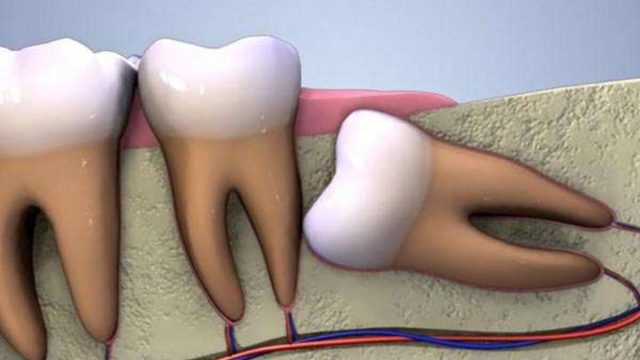

L’escroquerie des dents de sagesse et pourquoi vous avez besoin de vos dents de sagesse

(adsbygoogle = window.adsbygoogle || ).push({}); Que sont les dents de sagesse Les dents de sagesse, également appelées les troisièmes molaires, sont les dents les plus au fond de la bouche. Elles poussent généralement à la fin de votre adole ...